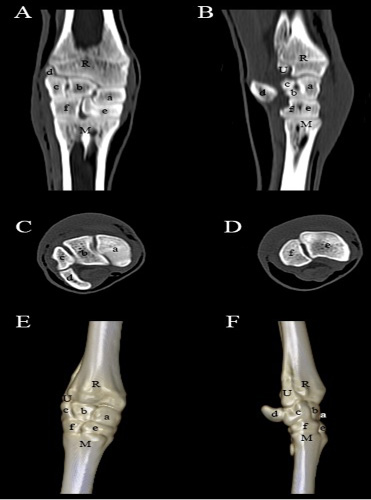

Computed tomography of the carpal joint. (A) Coronal view, (B) Sagittal scanning, (C) Axial scanning of the first raw of the carpal bones, (D) Axial scanning of the second raw of the carpal bones, (E) 3D image of the dorsopalmar aspect of the carpal joint, (F) 3D image of the lateromedial aspect of the carpal joint. R- Radius; U- Ulna; M- Metacarpus; a- Radial carpal bone; b- Intermediate carpal bone; c- Ulnar carpal bone; d- Accessory carpal bone; e- Fused second, third carpal bone; f- Fourth carpal bone.